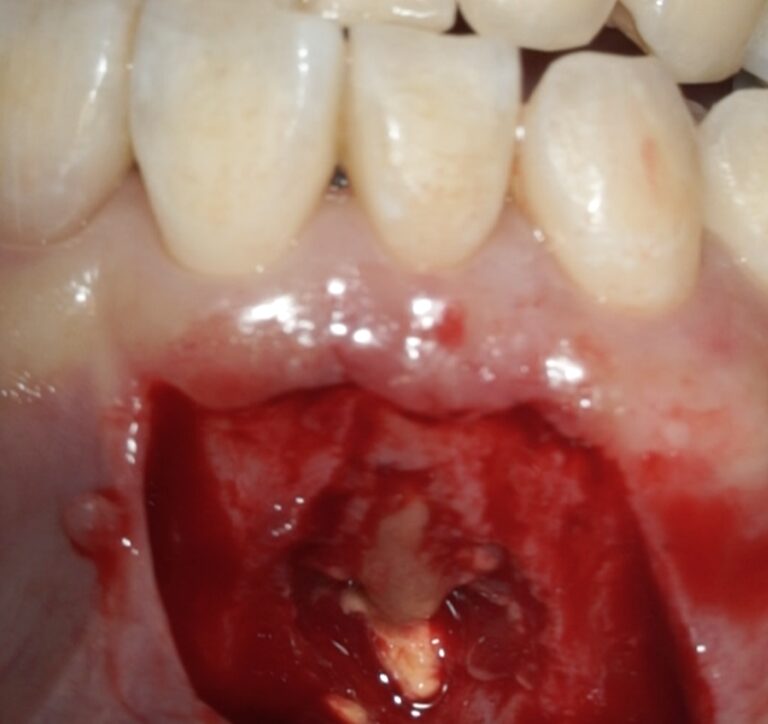

根管治療で治らなかった前歯の歯根端切除術(根尖孔外感染)

根管治療が効かない状態の歯、原因がいくつかありますがこのケースは根尖孔外感染(細菌が根管ではなく、根管の外の病巣部にコロニーを作って生息しているケース)のため根管治療で根管殺菌後も腫れが改善せず、歯根端切除術で病巣摘出を行い治癒へと導いたケースです。

前歯の歯茎が腫れている、という相談で来院されたケース

• 根尖孔外感染のため根管治療のみでは治らなかったケース

• 根管治療後4ヶ月、左上1の透過像(赤矢印、黒い影)は小さくなり治癒傾向が確認できますが、右上2(赤矢印)は以前より広がってきていて、腫脹の再発がありました。非治癒判定となり、次の治療法として歯根端切除術を行うこととなりました。歯根端切除術を行わない医院ではこの時点で抜歯が宣告されてしまうでしょう。

• 歯根端切除術で摘出した歯根と肉芽組織、黄色い色をした菌塊(細菌のコロニー)が多数見られました(黄色丸内のつぶつぶ)。これが非治癒の原因、根尖孔外に飛び出した感染源です。